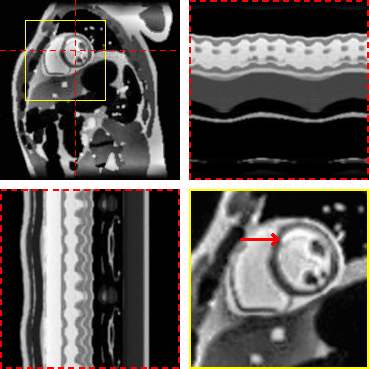

Figure 4: Exemplary real-time cine reconstructions. Each sub-figure illustrates an end-diastolic frame, temporal profiles, and a close-up on the heart. Red arrows show an area where differences in image sharpness are particularly apparent.

Figure 4 and Figure 5 illustrate the results for an exemplary real-time cine dataset and a free-breathing single-shot LGE dataset, respectively. Scoring results are given in Table 3 and Figure 6. M-DIP achieved highest scores in all considered criteria. Sharpness of real-time cines was scored significantly higher in M-DIP than in any other method. M-DIP and CineVN were scored equally in terms of noise/artifacts in the real-time cines, where only L+S received significantly lower scores than the other methods. In free-breathing single-shot LGE, M-DIP was scored significantly higher than both LR-DIP and L+S. Cine reconstruction took approximately 30 min with M-DIP and 45 min with LR-DIP, while LGE reconstruction took approximately 15 min with M-DIP and 10 min with LR-DIP.

Refer to caption

(a) CineVN (supervised)

(b) M-DIP

(c) LR-DIP

(d) L+S